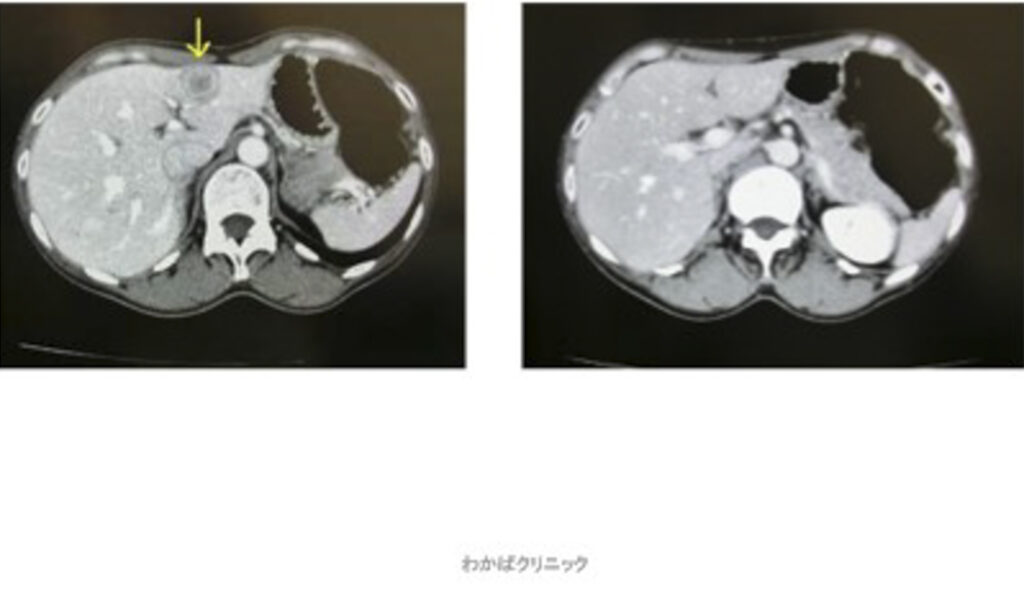

- 西洋医学的な効果判定(必ず必要です)

- CT・MRI・超音波検査 他